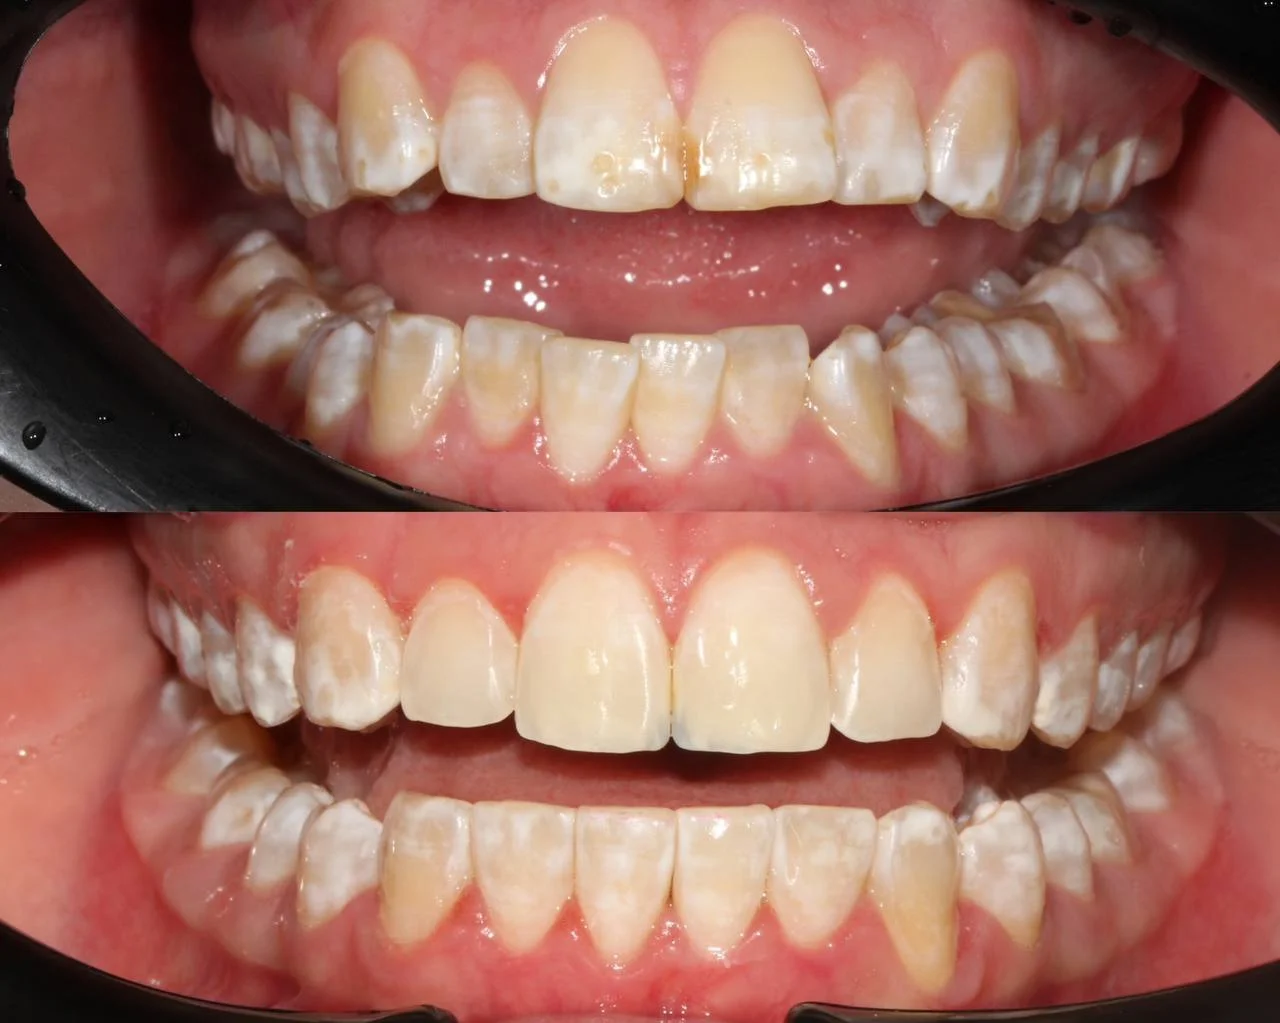

Лечение неправильного прикуса зубов на элайнерах Click Aligners за 23 месяца

Нарушение соотношения челюстей и неправильное положение зубов — зубные ряды смыкались некорректно, зубы стояли со смещением.

Прозрачные элайнеры Click на обе челюсти. Выровнять зубы и нормализовать смыкание. Основной набор — 20 кап. Срок — около 1 года.

Лечение заняло 23 месяца (октябрь 2023 — сентябрь 2025). Понадобился один дополнительный набор из 10 кап — итого 30 кап.

Зубы выровнены, смыкание нормализовано. Установлены несъёмные ретейнеры на обе челюсти, сняты сканы для ретенционных кап.

Проблема: Пациентку не устраивало положение зубов и то, как смыкаются челюсти. Зубы стояли неровно, ряды сходились неправильно.

Решение: Поставили прозрачные элайнеры Click — начали с компактного набора из 20 кап. Основной комплект сделал основной объем работы, но для финальной доводки понадобился дополнительный набор из 10 кап. Итого 30 кап за 23 месяца. Результат — зубы на месте, смыкание в норме. Зафиксировали ретейнеры на обе челюсти, сняли сканы для ретенционных кап.